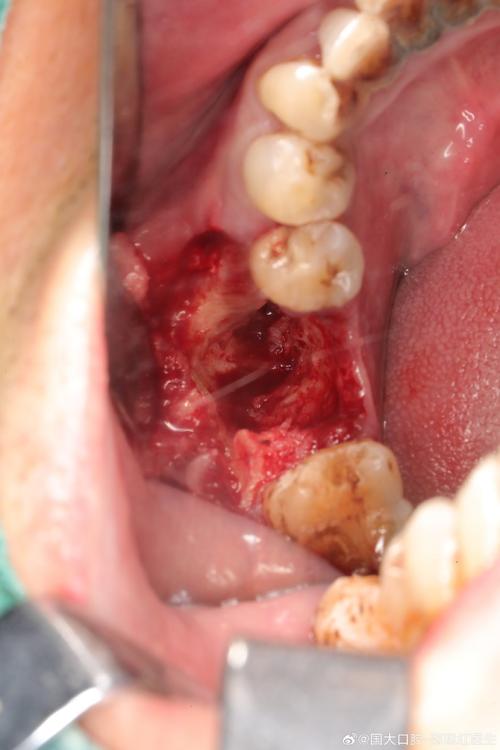

(图片来源网络,侵删)- 医生会进行专业的口腔检查,包括:

- 视诊:观察牙龈颜色、形态、肿胀、增生、退缩情况。

- 探诊:用牙周探针测量牙龈沟深度、是否有出血、溢脓、种植体松动度,探诊出血是炎症的重要指标。

- 拍X光片:评估牙槽骨状况(是否有骨吸收),检查种植体位置、基台和牙冠的密合度。

- 评估口腔卫生状况。

- 根据检查结果,医生会做出诊断,确定是正常愈合还是存在问题,以及问题的性质和严重程度。